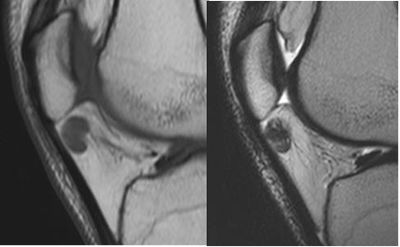

Fig 155. Hoffitis crónica.

A: RM sagital en T1 y B: RM sagital en T2. Imagen hipointensa en ambas secuencias, sobre la parte superior de la grasa infrapatelar, que corresponde a fibrosis residual.